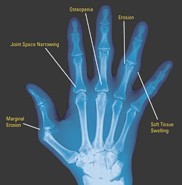

X - RAy:

Joint space narrowing

Soft tissue swelling

Erosions

Subluxations

Subchondrol osteopenia